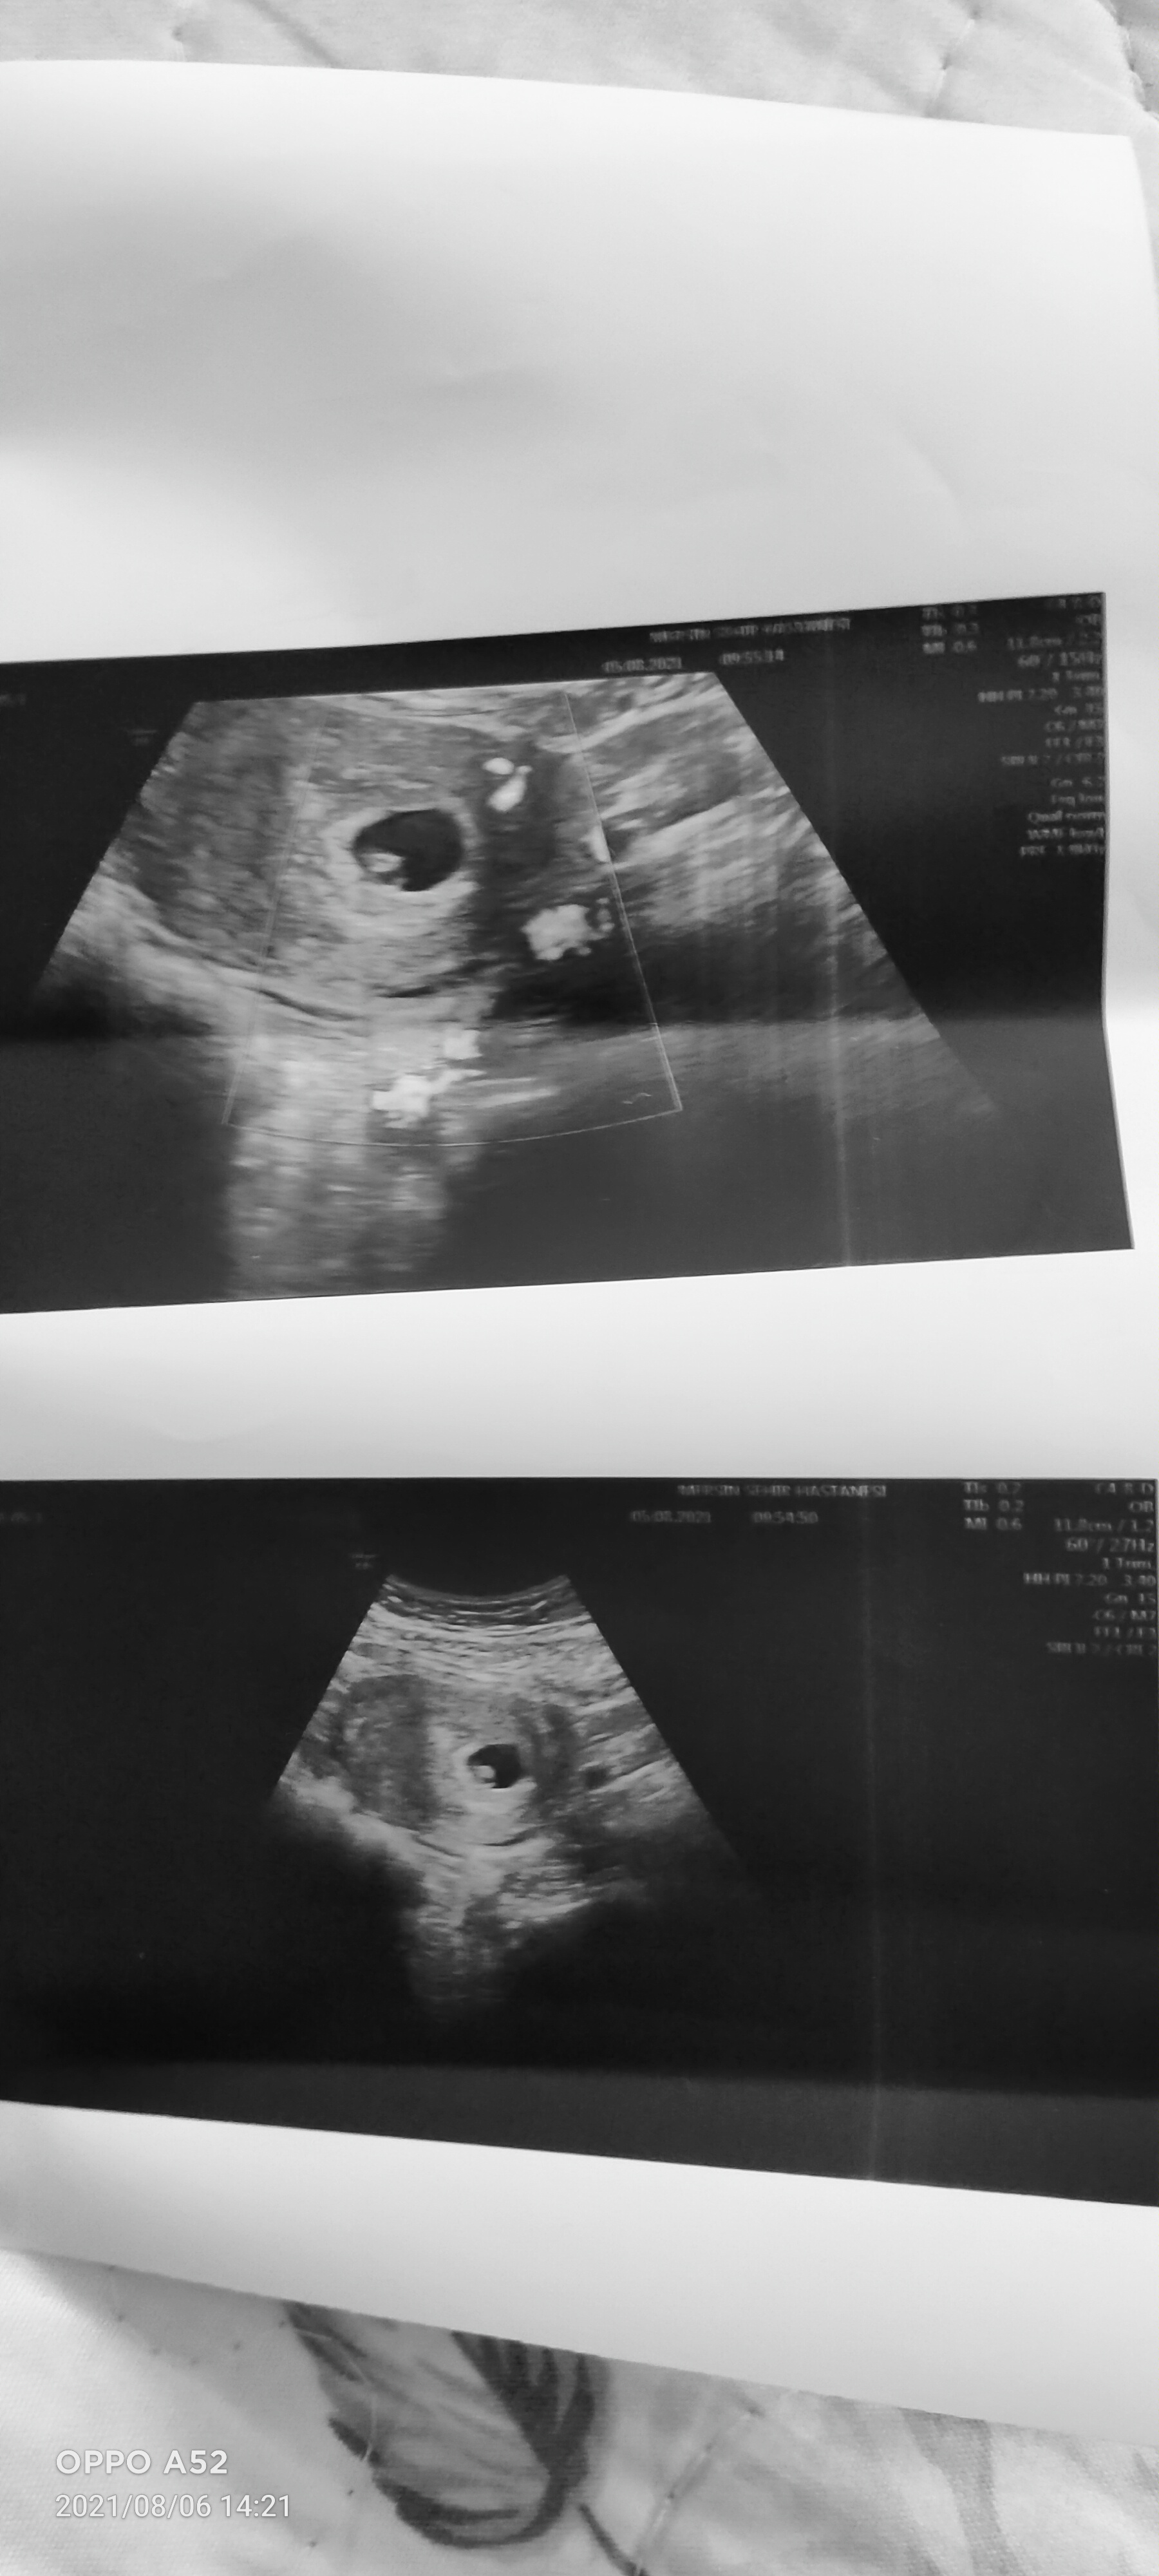

Benimki de sağ taraftaydi bu hafta şuan 20 haftalık en son kız dediler